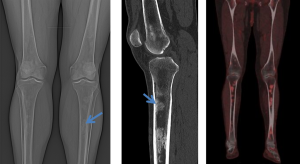

ERDHEIM-CHESTER DISEASE (ECD)

ECD is a rare non-Langerhans cell histiocytosis affecting multiple organ systems, typically presenting in adults in their 5th–7th decades with slight male predominance.

Diagnosis relies on biopsy supported by characteristic clinical and imaging features.

Retroperitoneal and renal involvement occurs in a significant proportion, with CT and MRI demonstrating bilateral perinephric and posterior pararenal soft-tissue infiltration, producing the classic “hairy kidney” appearance. Infiltrates are generally isoattenuating or iso- to hypointense to skeletal muscle with mild contrast enhancement; FDG uptake may be present but can be obscured by physiological renal activity. Chronic infiltration may result in renal atrophy.

Although both ECD and retroperitoneal fibrosis can lead to hydronephrosis, their distribution differs: ECD typically affects the perinephric fat and renal hila, whereas idiopathic RPF encases the anterolateral aorta and proximal ureters. Aortic encasement (“floating aorta sign”) and periureteric involvement may occur, but ECD usually spares the IVC and pelvic ureters. Additional distinguishing features include irregular perirenal infiltration and bilateral symmetric adrenal thickening.

Skeletal involvement, particularly of the femur, tibia and fibula, is seen in most patients, often causing bone pain [9].